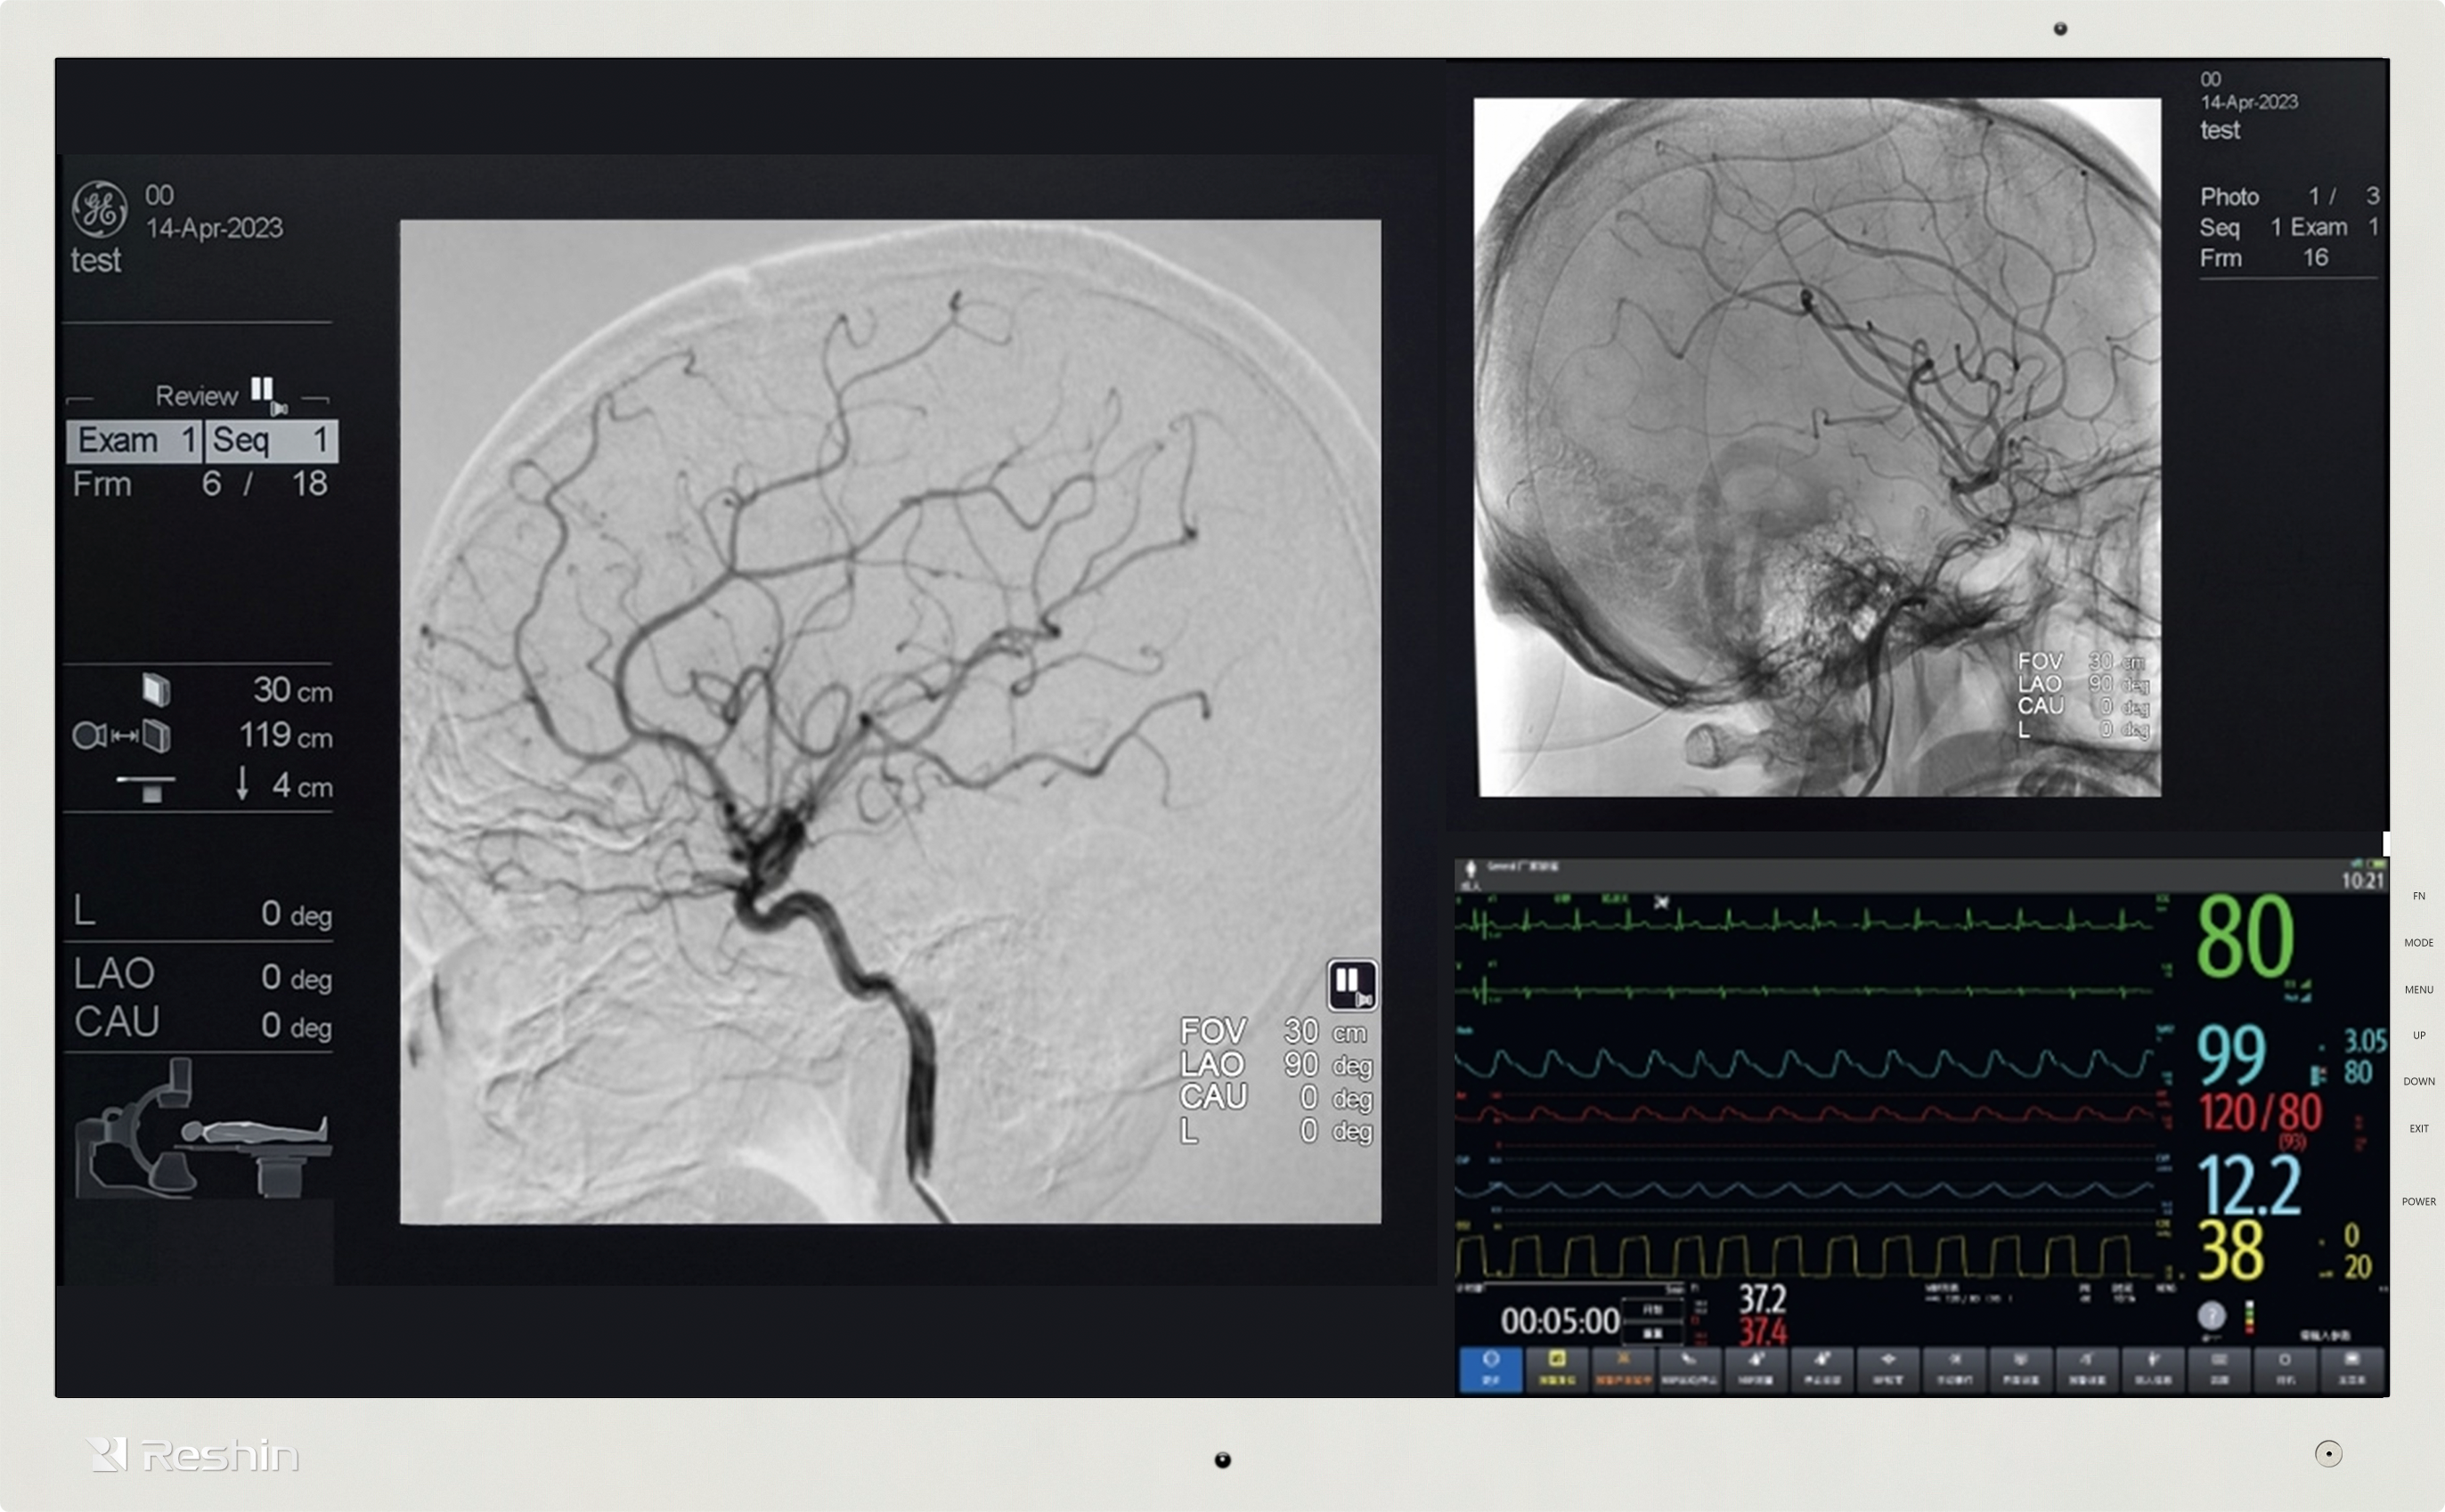

从技术原理来看,4K超高清的核心价值在于“信息承载量”的提升。以腹腔镜手术为例,医生通过直径不足1厘米的内镜观察体内组织,传统1080P显示器可能将0.1毫米的血管、神经末梢模糊成“色块”,而4K外科手术显示器能清晰呈现血管壁的纹理、神经纤维的分支走向。这种细节差异直接影响手术决策——在肝脏切除手术中,清晰识别肝内微小胆管,可避免术后胆瘘并发症;在神经外科手术中,精准区分肿瘤与正常脑组织边界,能最大程度保护神经功能,减少术后瘫痪、失语等风险。

手术视野清晰度对手术精度的影响,还体现在“操作容错率”的降低上。现代外科手术已进入“毫米级操作”时代,例如眼科白内障手术中,人工晶状体植入的位置偏差需控制在0.5毫米内;骨科关节置换手术中,假体安装角度的细微偏差可能导致术后关节活动受限。4K外科手术显示器能将手术视野放大后仍保持清晰,医生可通过显示器观察到器械与组织的微小接触状态,避免因视野模糊导致的操作失误。数据显示,使用4K外科手术显示器的微创手术,术中组织损伤率较1080P显示器降低约23%,术后恢复周期平均缩短1-2天。